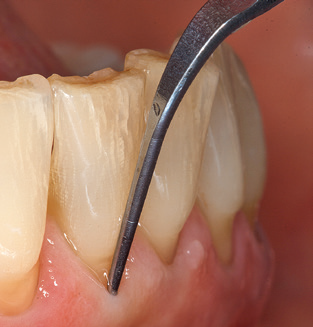

An array of special carbon, titanium and plastic curettes and scalers are available for the mechanical cleaning of implant surfaces by hand.(13-15) Overall, the efficacy of the biofilm removal with the available hand instruments is predominantly assessed as ineffective.(11) Whilst plastic curettes in particular have only a minimal detrimental effect on the implant surface and afford patients a high degree of comfort, their poor efficiency with regard to biofilm removal and their incapacity to remove calculus and subgingival concretions contraindicate their use.(16,17) Today, the use of carbon and titanium curettes is viewed as being more efficient, with the result that, if at all, these can be recommended for use as hand instruments.(11)

Fig. 4: Flexible probes with millimetre markings are recommended for the probing of dental implants (e.g. Colorvue Kit PCV11KIT6, Hu­Friedy). – Fig. 5a and b: A straight working tip (1P, W&H Dentalwerk Bürmoos GmbH) is a suitable instrument for use on all natural teeth. – Fig. 6: Curved working tips (3Pr/3Pl, W&H Dentalwerk Bürmoos GmbH) lend themselves to the processing of difficult-to-reach areas of the tooth and root surfaces (e.g. furcations). – Fig. 7: The tapered, hexagonal implant cleaning tip (1I, W&H Dentalwerk Bürmoos GmbH) permits atraumatic and efficient cleaning of the crown and abutment surfaces. – Fig. 8: Titanium and carbon curettes are suitable instruments for the manual cleaning of the implant surfaces.

Following machine cleaning of the tooth and implant surfaces, the surfaces of the natural teeth are cleaned manually using standard hand instruments. When performing manual cleaning, particular attention must be given to maintaining the correct angle of application, appropriate sharpness, good support and working with the curette from apical to coronal. Either titanium or carbon curettes should be used for post-cleaning of the implant structures (Fig. 8). In addition to the use of ultrasonic devices, power jet devices can also be used in conservative dentistry. However, it must be taken into consideration that these procedures are not suitable for removing hard deposits and thus they cannot replace the use of hand instruments and ultrasonic instruments completely. In all cases, cleaning is followed by mechanical polishing of the accessible tooth and implant surfaces with polishing cups and polishing compounds (Fig. 9).